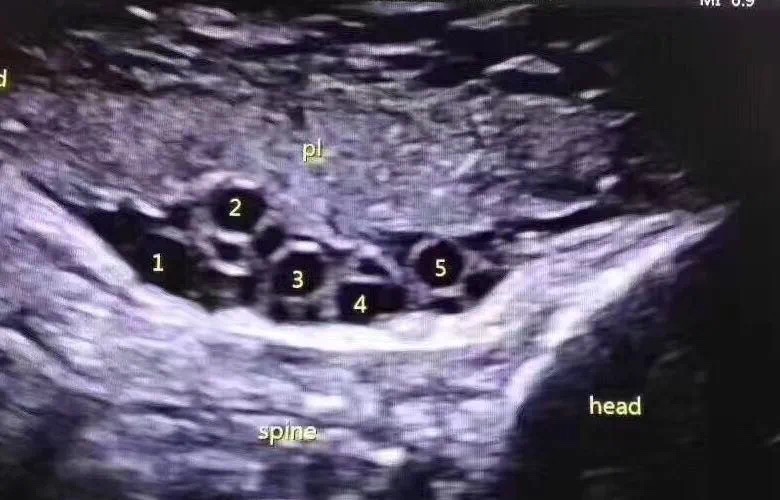

绕颈5圈!